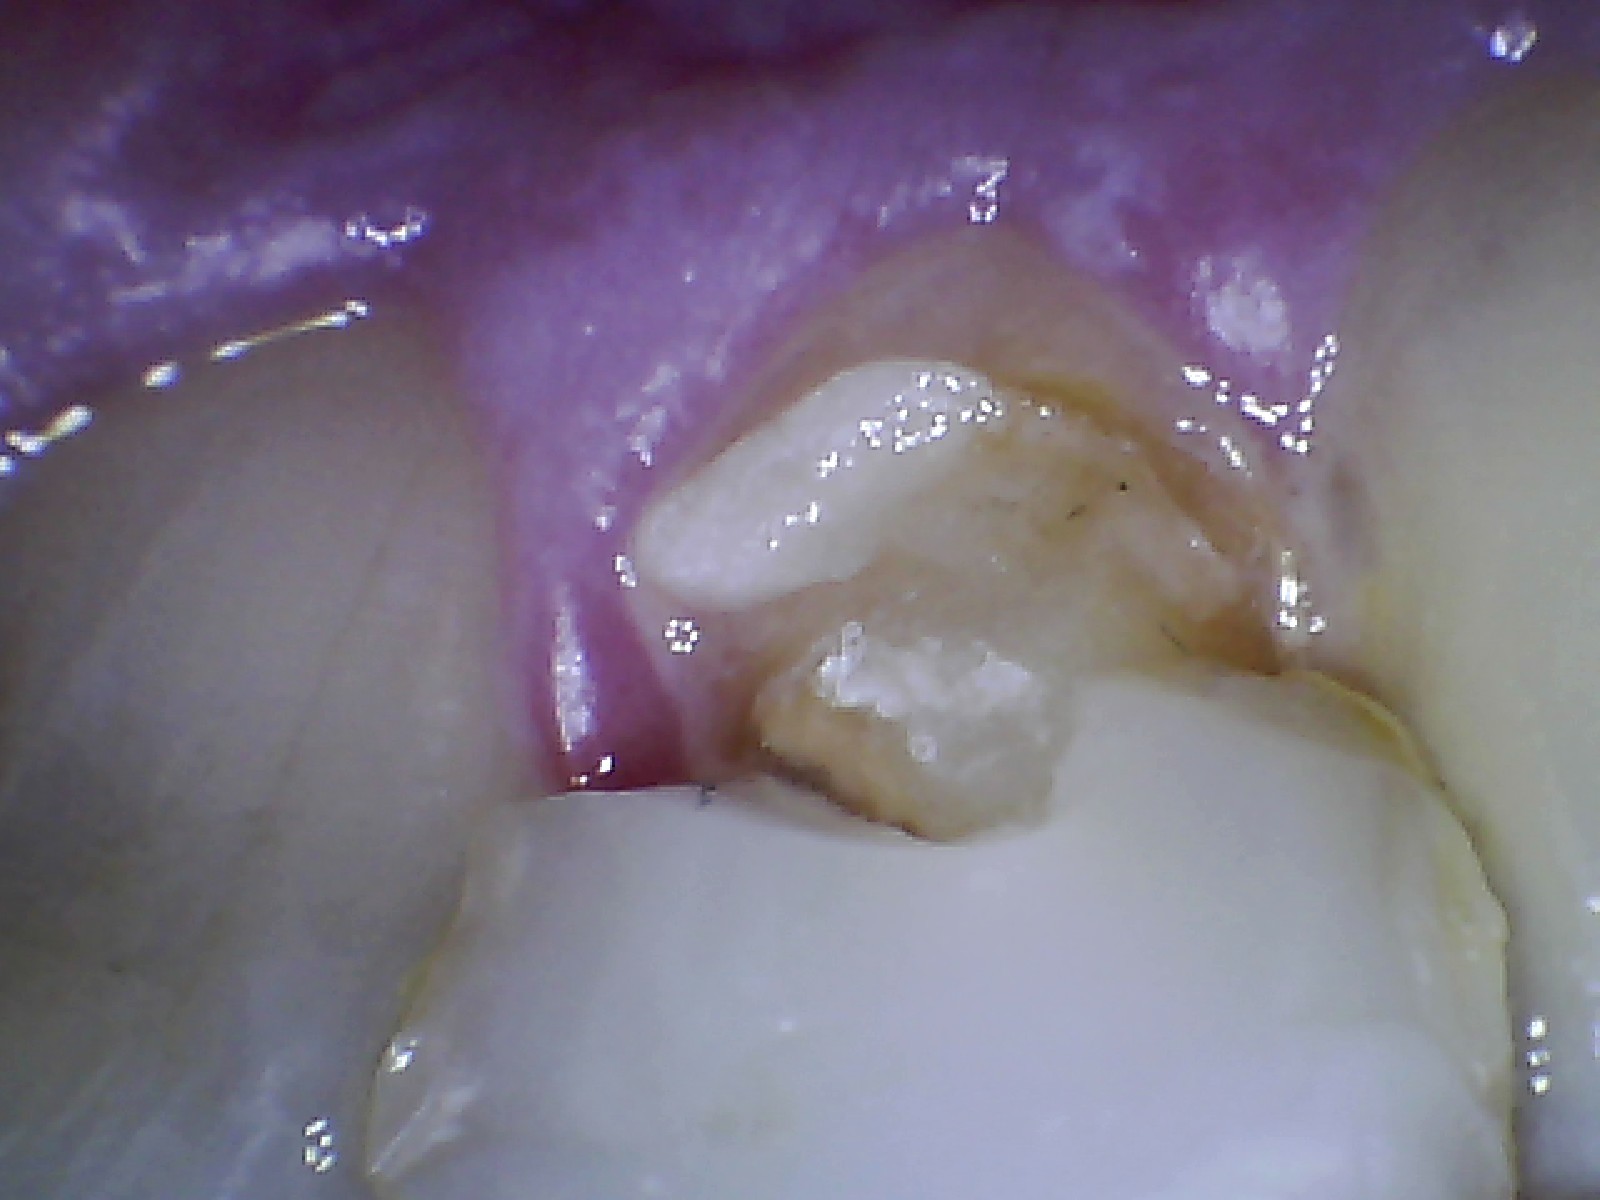

Dental Case Study Front Tooth Broken To Gum Line; Restore With Crown Crown On Front Tooth Fell Off Losing a dental crown when there is no tooth left can be a concerning situation, but it’s essential to take prompt action. A loose crown can be a dental emergency and should be repaired by a dentist as soon as possible. Find out what to do if your crown falls out and how to avoid it with proper care and. Crown On Front Tooth Fell Off.

Tooth Crown Procedure Front Tooth Crowns for Broken Teeth (LIVE